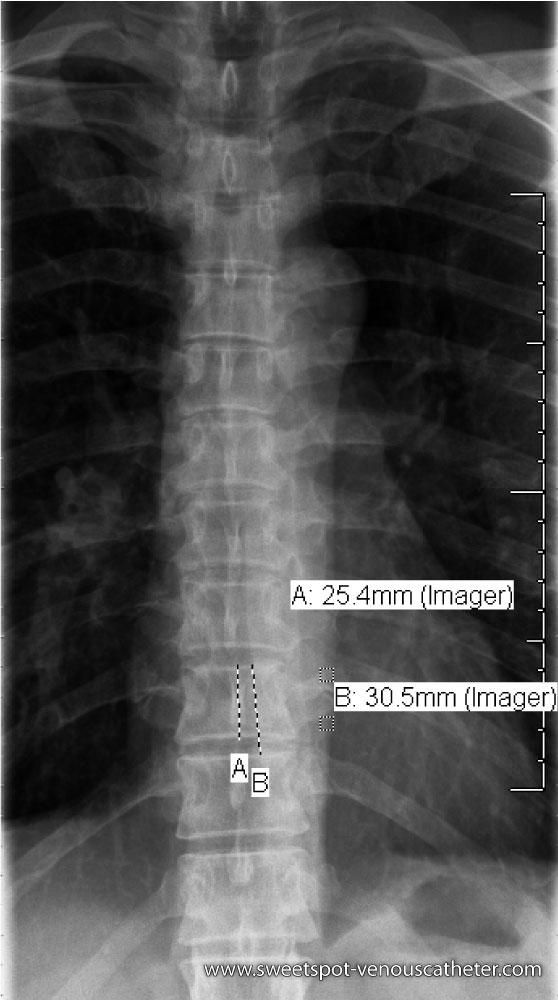

Figure - 13

"Vertebral body is internal ruler." Dorsal spine X-ray average 2.5cm height lower dorsal area. 3cm = distance between adjacent superior (or inferior) plates. |

Coronal reformation CT. Example of average height of dorsal vertebral body ≈ 2.5cm "internal ruler." |